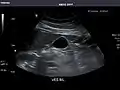

Spleen: Normal in size.

Spleen